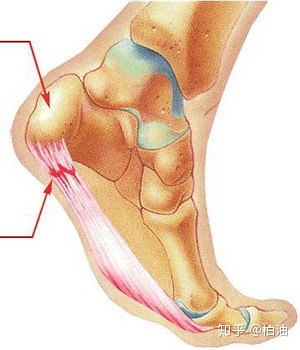

此外,内侧足弓的形成还需要足底软组织的参与,包括足底长韧带、弹性韧带、足底筋膜等。

这些组织是否处于正常的位置、是否维持正常的功能对于足弓的稳定至关重要,我们常说的扁平足指的就是维持足弓的内侧楔骨下移造成的,同时距骨和足舟骨向内侧移动,严重的情况下距骨的高度也会下降。这也是为什么有扁平足的同学,在双脚并拢站立时,两只脚的脚踝内侧会碰到一起。

距骨内移的情况下,跟骨会内倾,因此我们在后面也能通过跟腱的走向来判断足弓的情况。

正常足弓时,跟腱是垂直地面的;扁平足则往往会使得跟腱倾斜或呈现弧线。